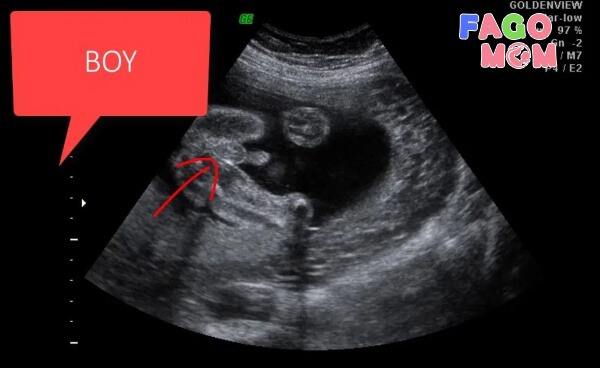

Nhịp tim không liên quan đến giới tính thai nhi mẹ nhé, để biết chính xác giới tính, mẹ nên dùng các biện pháp khác như siêu âm. Khi mẹ đi siêu âm, đặc biệt là siêu âm 4D, máy móc hiện đại, bác sĩ giàu kinh nghiệm, tư thế nằm của con thuận lợi, thì mẹ hoàn toàn có thể biết được con là trai hay gái.

Các cơ quan khác như dạ dày, ruột non, ruột già, gan, tuyến tụy... cũng phát triển nhanh và bắt đầu đi vào hoạt động. Nhờ đó, cơ thể bé yêu có thể thực hiện chức năng chuyển hóa năng lượng và bài tiết dễ dàng. Nếu thai nhi là con gái, giờ đây, buồng trứng đã có hơn 2 triệu trứng. Tuy nhiên, việc xác định giới tính dựa vào hình ảnh siêu âm thai nhi 13 tuần tuổi vẫn chưa thực sự chính xác nên mẹ cần đợi tới những tuần tiếp theo để kiểm tra chắc chắn hơn.